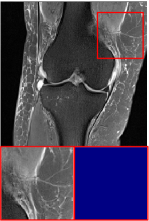

Public Dataset. The public dataset employed is the FastMRI Knee [43], where the reference contrast is PD, and the target contrast is FS-PD. We selected 1600 slices with a training, validation, and test set split ratio of 7:1:2.

Figure 5 provides the qualitative comparison of the various methods on the four datasets at a scale of 4. The top, second, third, and bottom rows are the SR results under the FastMRI, clinical brain, clinical tumor and clinical pelvic datasets, respectively. The red boxes indicate the zoom-in region of complicated anatomical structures along with their corresponding error maps. Note that the brighter textures in the error maps, the lower the quality of the reconstructed images. As can be seen, compared to methods based on Transformers and CNNs, diffusion-based methods like DisC-Diff and DiffMSR (Ours) are capable of reconstructing high-realistic images with promising reconstruction metric scores (PSNR and SSIM). Nevertheless, while DisC-Diff can reconstruct high-precision MR images, it does not preserve the structure present in the original HR images, introducing some additional information that can affect medical diagnosis. In contrast, our method combines DM and PLWformer, which can preserve the original image’s structure while restoring high-frequency information.

In this section, we present more visual qualitative comparisons. Figures 8, 9, 10, and 11 show the reconstruction results of each method in FastMRI, clinical brain, clinical tumor, and clinical pelvic, respectively. As can be seen, although DisC-Diff can reconstruct MR images with high-frequency information, it fails to preserve the structure and content of the original Target HR image effectively, resulting in image distortion. In contrast, our proposed DiffMSR can restore high-frequency information while preserving the structure of the original HR image, indicating the effectiveness of the joint use of DM and PLWformer.